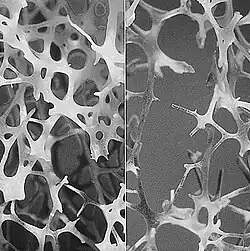

Физиологическая костная резорбция является неотъемлемой частью функционирования кости, которая постоянно обновляется за счёт двух противоположных процессов — разрушения и образования костной ткани. Костная ткань — это динамическая система с активным метаболизмом. Последовательная цепь процессов удаления участков старого костного матрикса и замещение его новым носит название ремоделирования костной ткани или костное ремоделирование.[2]:10 В детском возрасте за счёт именно этих процессов происходит рост и увеличение скелета, в этот период образование костной ткани естественным образом преобладает над резорбцией. Локальным проявлением физиологической костной резорбции также может служить процесс прорезывания зубов, в котором продвижению зубного фолликула предшествует активная резорбция челюстной костной ткани. В сформировавшемся скелете (зрелый возраст) процессы рассасывания старой кости и образования новой в целом уравновешены. Однако с возрастом процессы ремоделирования постепенно смещаются в сторону резорбции, и количество рассосавшейся костной ткани начинает преобладать над вновь образованной, в результате чего и происходит постепенная потеря костной массы, что может приводить сначала к возрастной остеопении, а затем и к — остеопорозу.

Процесс перестройки (ремоделирования) костной ткани происходит в отдельных участках кости, которые носят название «единицы ремоделирования» или базисной многоклеточной единицы (БМЕ). В этих участках локально протекают сопряжённые процессы резорбции и образования кости. Активизация процесса начинается с запуска неких сигналов-стимулов, по которым остеокласты и другие мононуклеарные клетки мигрируют к определённому участку костной ткани и прикрепляются к костной пластине. Остеокласты продуцируют протеолитические ферменты, лактат, ионы водорода, которые разрушают (гидролизуют) белковый матрикс и растворяют минеральную часть кости, при этом выделяется свободный кальций и другие компоненты.[1]:85—87 В результате такой активности в губчатой кости образуются углубления до 40 мкм, имеющие форму блюдца, а в кортикальной кости — конусовидные пустоты диаметром около 150 мкм и длиной до 2,5 мм. Продолжительность фазы резорбции длится от 27 дней в кортикальном слое кости и до 42 дней в губчатой ткани. Этот период резорбции включает в себя и фазу реверсии длительностью 4 дня в кортикальной и 9 дней в губчатой тканях кости. Фаза реверсии является переходным периодом, в который процесс резорбции сопряжён с процессом формирования кости. В период реверсии образуется цементирующая линия (или клей), которая соединяет новую и старую кость. Цикл ремоделирования завершается фазой формирования кости, которая длится от 95 до 130 дней. Вновь образующийся участок костной ткани носит название базисной структурной единицы (БСЕ) или остеона. Остеобласты образуют неминерализованный органический матрикс (остеоид), который через 25—35 дней начинает минерализоваться.[1]:87 Ремоделирование кости начинается ещё в пренатальном периоде и продолжается на протяжении всей жизни. Активность ремоделирования костной ткани и скорость костеобразования находятся на высоком уровне вплоть до достижения индивидом половой зрелости, затем этот уровень снижается. В среднем к 20—23 годам жизни достигается пик костной массы, который поддерживается на заданном уровне до 30—35 лет у женщин, а у мужчин — несколько дольше. В этот возрастной период ремоделирование кости имеет циклический равномерный характер, в котором процессы разрушения и образования кости уравновешены, что обеспечивает обновление кости и сохранение костной массы, а также поддерживает минеральный обмен. С возрастом интенсивность ремоделирования костной ткани резко снижается, это происходит после 35 лет у женщин и 50 лет у мужчин. Резорбция костной ткани идёт с бо́льшей скоростью, чем костеобразование, начинается постепенная потеря массы кости, что становится причиной возрастного уменьшения костного объёма и снижения минеральной плотности костной ткани (МПКТ).[2]:12

нормальная и разрушающаяся

Широкое распространение имеет обычная рентгенография. Однако визуальная оценка рентгенограмм скелета является субъективной и малоинформативной. Остеопороз по рентгенограммам выявляется лишь на поздних стадиях, когда происходит потеря уже 30 % костной массы и более. Существуют радиоизотопные методы исследования скелета — сцинтиграфия, которая также не способна выявить остеопенические состояния, как правило, предшествующие остеопорозу.[2]:67-73 Наиболее информативным методом костной денситометрии является двухэнергетическая рентгеновская абсорбциометрия (DEXA). Это низкоэнергетический метод с высокой точностью измерений и малой лучевой нагрузкой на пациента. Он позволяет количественно определить минеральную плотность костной ткани (МПК) в различных отделах скелета и общую костную массу, а также выявить их снижение уже при 2-5 % потери.[4]:45 Расчёт условных единиц и величины стандартного отклонения от среднестатистических показателей позволяет количественно различить как варианты нормы, так остеопению и остеопороз.[2]:81 Метод компьютерной томографии расширяет возможности исследования костной ткани. Его преимущества — это высокая воспроизводимость, меньшее облучение, высокая точность исследования и возможность раздельной оценки губчатой и компактной кости.[2]:82 В целом лучевая диагностика позволяет в большей степени оценить состояние костной ткани по минеральному компоненту, но является менее информативной в отношении органической составляющей. Кроме того к её недостаткам можно отнести облучение пациента и относительную дороговизну обследования.